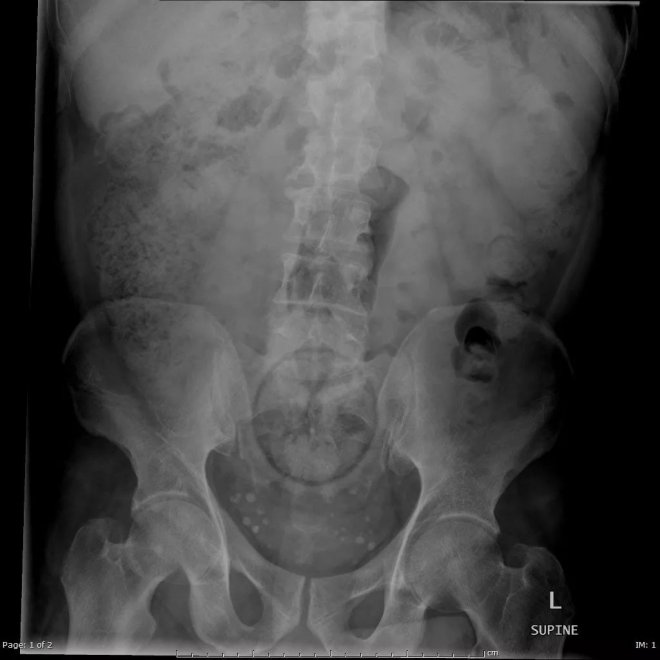

大型玩具

醫療診斷為「直腸異物」